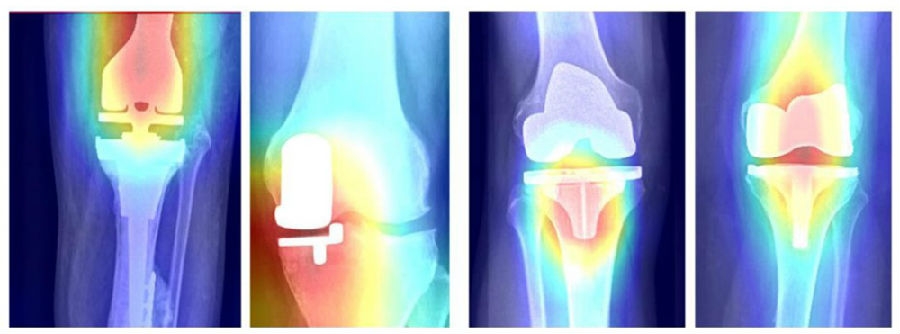

Karnuta等[8]使用350万张X线平片训练、验证和外部测试一个人工智能方法来自动识别TKA假体, 通过深度学习系统进行1000个训练周期后,系统在744张前后位X光片的外部测试数据集中,可以自动区分所有9种假体,AUC为0.989,准确率为97.4%,灵敏度为89.2%,特异性为99.0%。每张图像识别时间平均0.02秒。类似地,有学者[9]使用200万张X线平片训练、验证和外部测试同样地人工智能方法来自动识别THA假体。通过深度学习系统进行1000个训练周期后,系统在588张前后位X光片的外部测试数据集中,可以自动区分8种假体,AUC为0.991,准确率为97.9%,灵敏度为88.6%,特异性为98.9%。每张图像识别时间平均0.02秒。作者认为, 用于识别膝、髋关节置换术假体的人工智能软件表现出色,证明人工智能在临床应用的价值所在,并具有协助膝、髋关节翻修术前计划的巨大潜力(图4、5)。

图4 膝关节假体的样本热图,说明人工智能模型的识别重点

图5 热图图像展示人工智能算法感兴趣的假体特征,有目的地将前后X射线的图像增强为不完美的渲染图

假体特点如下:DePuy SROM(左上)、DePuy Corail(右上)、Stryker Accolade(左下)和Stryker Restoration Modular(右下)